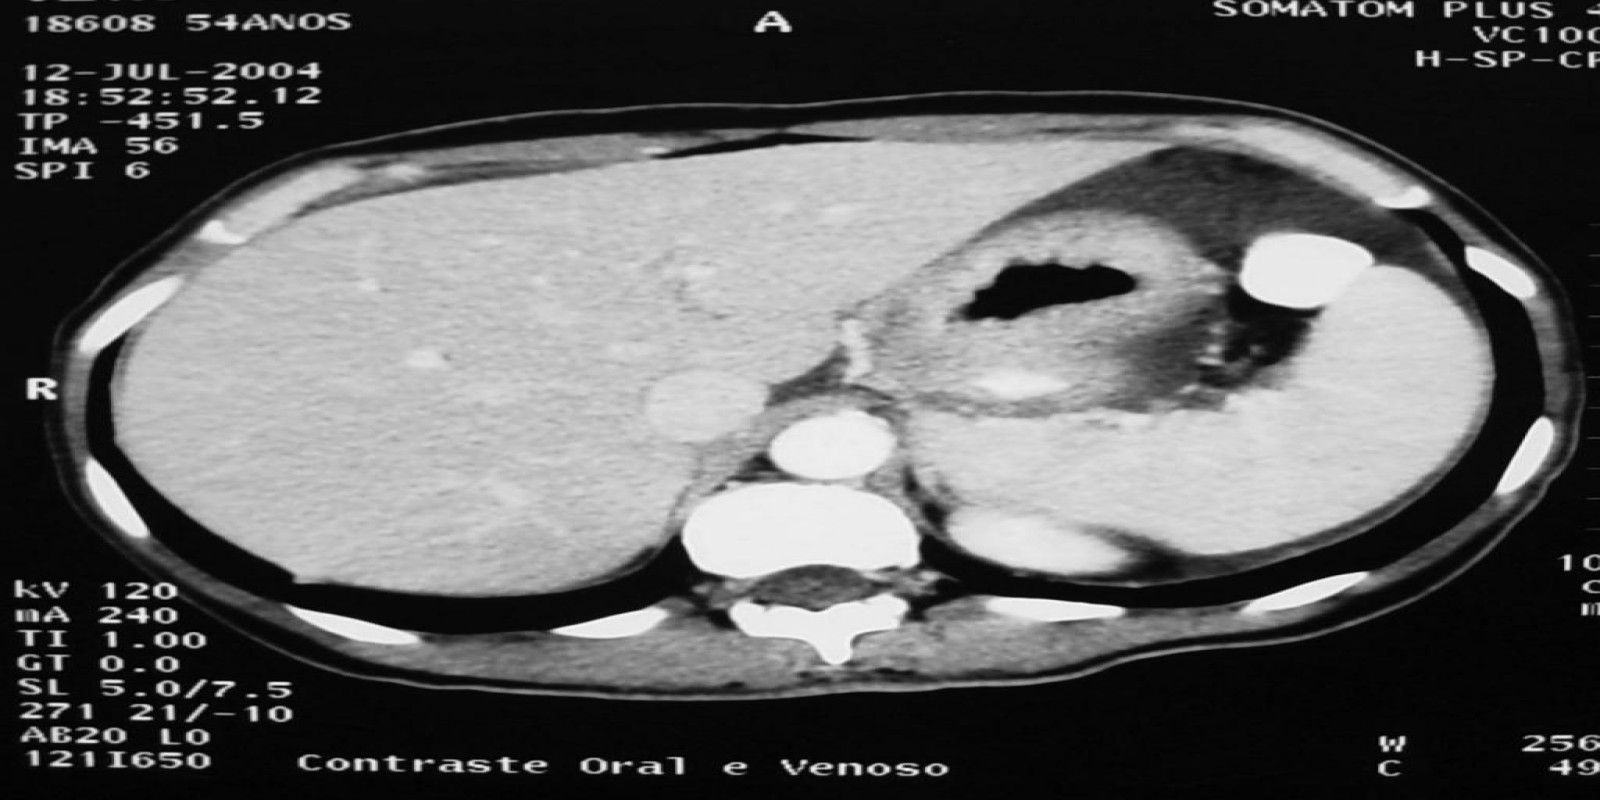

Caso Código 149B de Câncer Gástrico

Cod.: 149B